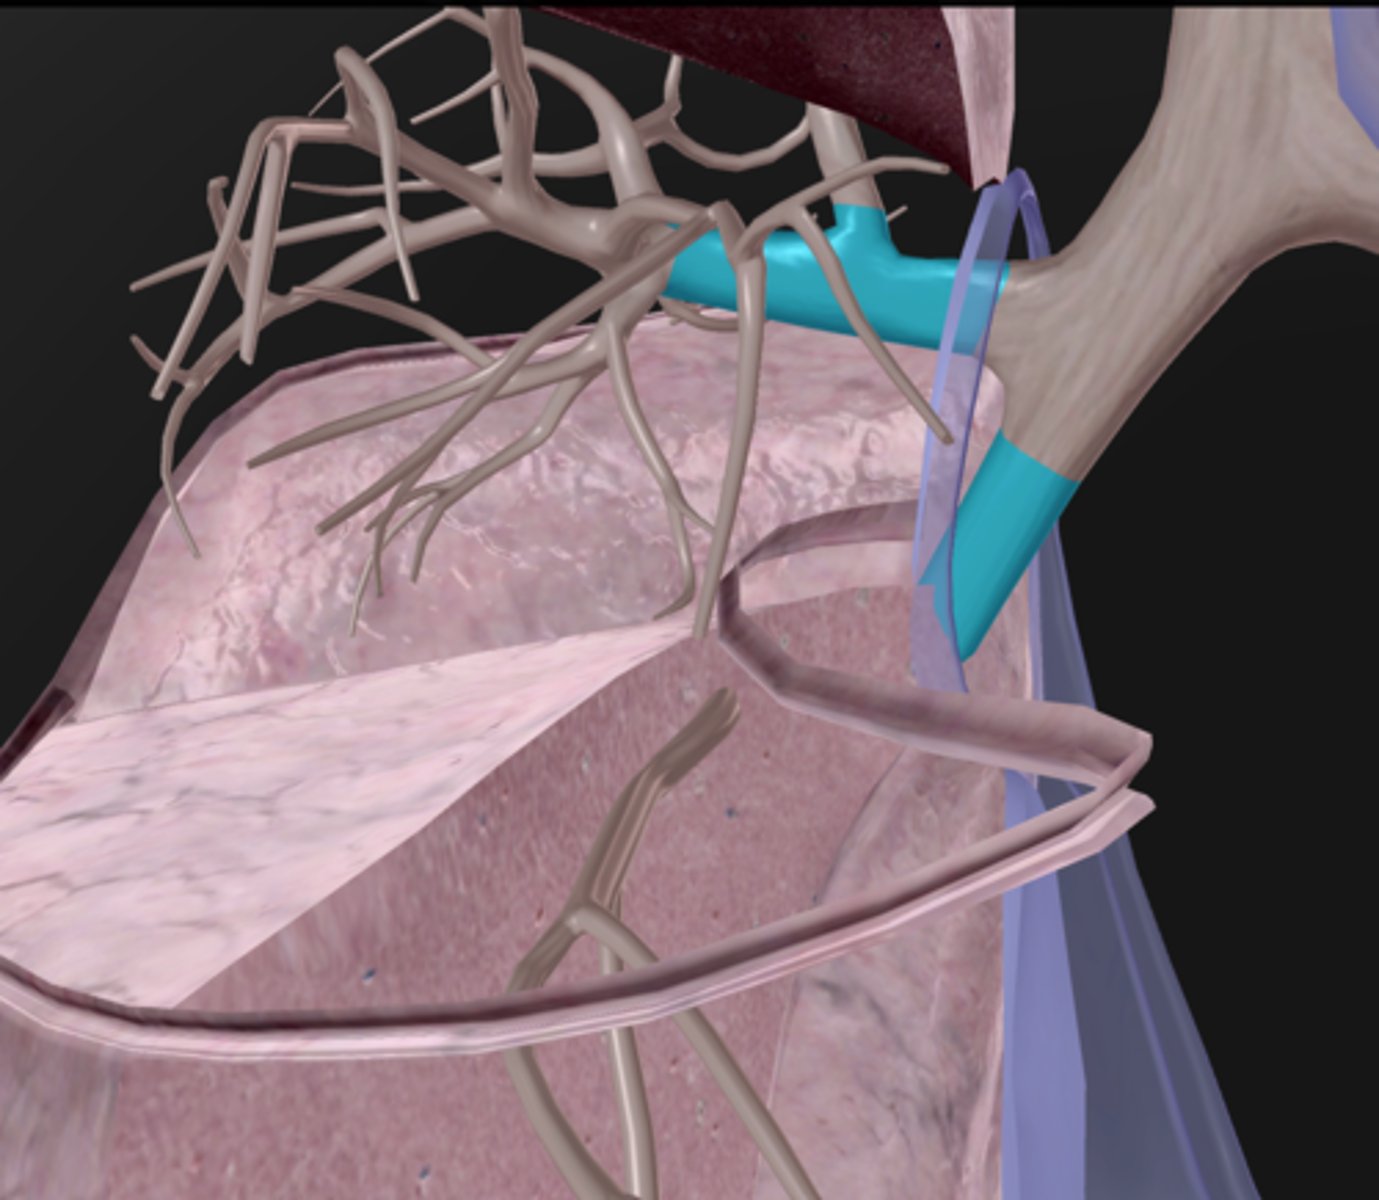

Pulmonary arteries

Pulmonary veins

Hilum